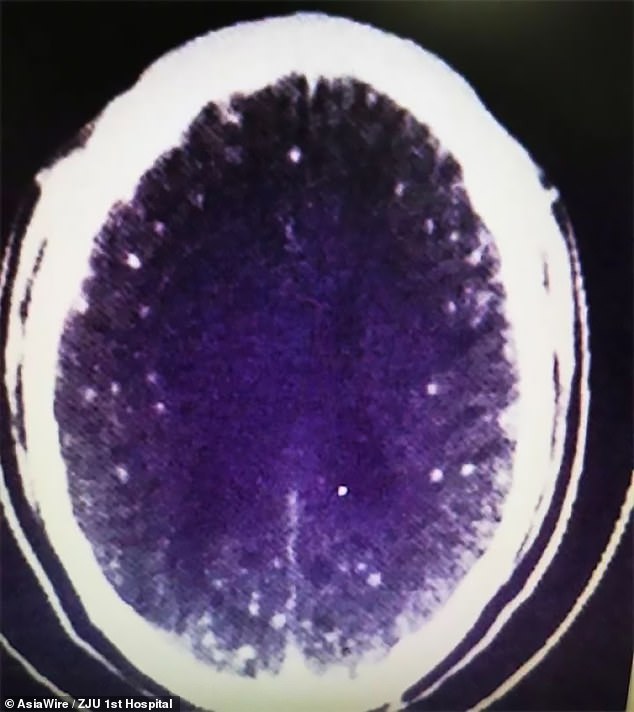

Dr Huang Jianrong, from the Affiliated Hospital of Zhejiang University School of Medicine, ordered brain and chest MRI scans.

These revealed that Mr Zhu’s brain and chest were riddled with cysts of the pork tapeworm.

Dr Huang said: ‘He not only had numerous space-occupying lesions in his brain, he also had cysts in his lungs and chest muscles.

‘Different patients respond differently to the infection depending on where the parasites occupy.

‘In this case, he had seizures and lost consciousness, but others with cysts in their lungs might cough a lot.’